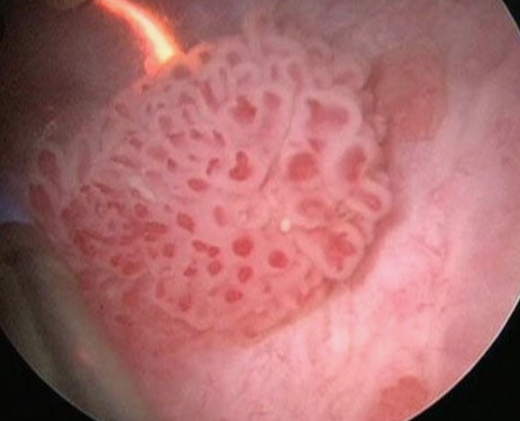

방광암의 가장 대표적인 전조증상은 통증이 없는 혈뇨입니다. 방광암 환자의 80~90%에서 이 증상이 첫 번째로 나타나며, 약 85%의 환자가 혈뇨 증상을 보입니다.

소변 색깔은 간장색에서 선홍색까지 다양하게 나타날 수 있으며, 때로는 소변이 녹색으로 변하기도 합니다. 중요한 점은 혈뇨의 정도가 암의 진행 정도와 반드시 일치하지 않는다는 것입니다.